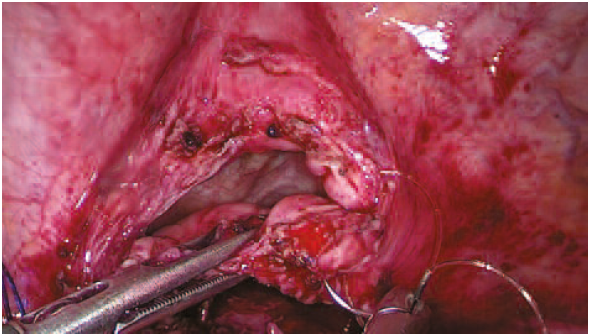

При осмотре спаечный процесс в брюшной полости не выражен, однако в области свища визуализировалось выраженное воспаление. Рассекли брюшину в области пузырно-маточной складки, дальнейшее выделение производили тупым и острым путем при помощи ультразвукового диссектора и хирургического аспиратора-ирригатора (рис. 2). В процессе разделения вскрыт МП в области свища и вскрыта матка в области передней стенки. Дефект стенки матки ушит двумя рядами швов непрерывным швом нитью «Стратофикс» 3-0 (рис. 3). МП осмотрен со стороны слизистой, иной локализации свища не выявлено. Произведено ушивание стенки МП двухрядным непрерывным швом нитью «Стратофикс» 3-0 (рис. 4, 5). Осуществлен контроль гемостаза, снят карбоксиперитонеум, удалены рабочие и оптический троакары, ушит дефект в области пупочного кольца, швы на кожные раны. Дренирование МП осуществлялось уретральным катетером Фолея №20. В послеоперационном периоде проводили профилактику тромбоэмболических осложнений, обезболивание парентеральными анальгетиками.

Рис. 3. Ушита стенка матки (по типу метропластики).

Fig. 3. The wall of the uterus is sutured (by the type of metroplasty).